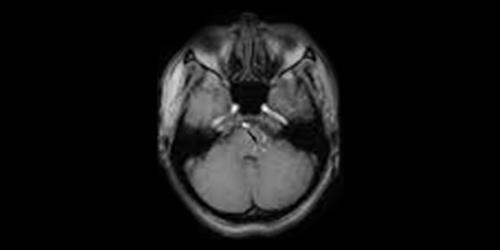

2: Görüntüleme yöntemlerinden beyin Magnetik Rezonans (MR) tekniği hem primer hemde sekonder yüz seyirmelerine neden olan sebebi ortaya çıkarmaktadır. Burada bu tekniği kullanırken özellikle yüz sinirine ait bir araştırma ve inceleme yapmak önemlidir. Bir normal beyin MR inceleme tekniğinde bu hastalığın nedenini çoğu kez gösteremez.